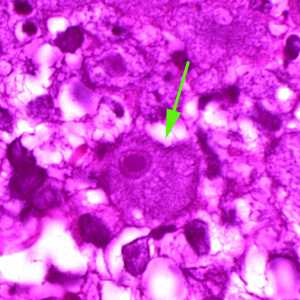

Figure F: A single trophozoite (green arrow) of B. mandrillaris in brain tissue, stained with H&E.